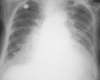

Q

What is the red arrow indicating?

Is this a normal finding on a CXR?

A

• Gastric bubble

• This is a normal finding on a CXR

Free air: Instead of the air being contained inside the stomach to the unitlateral side of the diaphgram, air will be displaced bilaterally on both sides of the diaphragm.